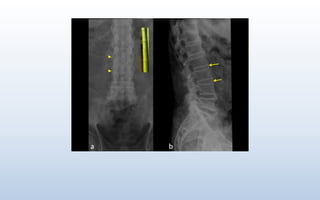

X- Ray findings in the Spine

• Shiny Corner Sign/ Ivory Corner/ Romanus Lesion

• Vertebral Body Squaring

• Dagger Spine Appearance

• Trolley track Sign

• Bamboo Spine

Shiny Corner Sign/ Romanus Lesion/ Ivory Corner

Triangular regions of sclerosis are classically seen at the superior and inferior vertebral endplates

anteriorly (corners). This occurs as a response to inflammatory Romanas Erosion which may be

seen concomitantly with the sclerotic "shiny corners".

It represents reactive sclerosis secondary to inflammatory erosions

Vertebral Body squaring

Straightening of the anterior border of the

vertebral body due to a combination of corner

erosion with resorption at the enthesis.

Dagger Sign

Occurs due to supraspinous & interspinous ligament ossification, creating a solid, midline,

vertical density which simulates a dagger.